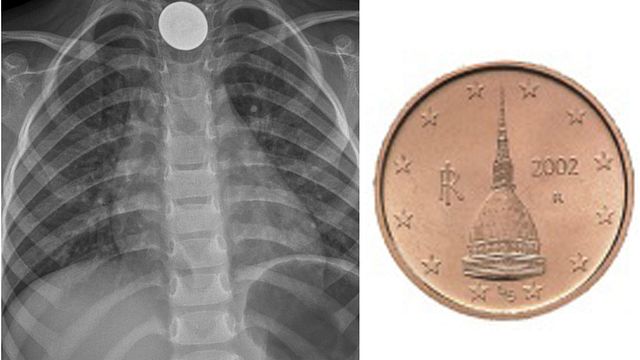

Un bambino di 4 anni ha ingoiato una monetina da due centesimi mentre stava giocando. La madre, immediatamente accortasi di quanto accaduto, l'ha portato al pronto soccorso dell'ospedale di Omegna (Verbano Cusio Ossola), ma qui avrebbe ottenuto come suggerimento solo quello di rimanere in vigile attesa. "Non solo. Mi hanno detto anche di farlo mangiare - ha raccontato mamma Barbara -. Anzi un'infermiera mi ha dato dei grissini. Secondo lei il cibo avrebbe aiutato il transito della monetina, ferma nella parte alta dell'esofago. Non mi sono fidata e non l'ho fatto. Per fortuna direi, avrei potuto ucciderlo". Il piccolo, infatti, ha continuato a star male ed è stato decisivo un secondo consulto a Verbania e la seguente corsa a Novara per l'operazione.

Il piccolo, una volta a casa, ha continuato a lamentarsi, non riusciva a chiudere la bocca, e sbavava. Così i genitori hanno deciso di portarlo in un altro ospedale, a Verbania. "Solo in quel momento abbiamo scoperto che da Omegna avevano chiamato Verbania per un consulto e gli avevano consigliato di fare una lastra - ha spiegato ancora la donna -. Cosa che non è stata fatta. Anche al Dea di Verbania non volevano, ma arrivati in pediatria l'hanno fatta subito".

Con la lastra in mano la famiglia è stata trasferita d'urgenza a Novara per permettere l'intervento di rimozione della monetina. "Ci hanno spiegato che poteva soffocare o anche lacerarsi l'esofago. Poi a Novara con un sondino introdotto dalla bocca in anestesia totale gli hanno asportato la monetina. Al risveglio stava bene e dopo sette ore di osservazione siamo tornati a casa. Sto pensando se denunciare tutto ai carabinieri. Per ora ho ricevuto le scuse del primario del Dea e della caposala. Se ci penso mio figlio ha rischiato di morire strozzato", ha concluso.